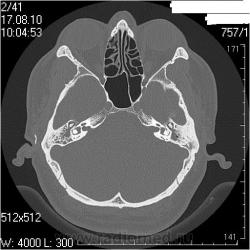

Андрей Юрьевич, извиняюсь за столько вопросов,тема для меня неизведанная, но пузырьки воздуха в патологическом компоненте/субстрате/массах слева не могут быть признаком гнойного процесса?

С уважением, С.Н. Нагорный

Гнойного, т.е. газообразующего? Нет. Это атмосферный воздух. Он должен быть в барабанной полости в норме, а тут и патологического содержимого меньше, чем справа + неполный блок слуховой трубы + перфорация барабанной перепоки

А засада (что НЕ ТАК), для меня здесь вот в чем. У пациента клиника левостороннего отита (многолетний анамнез, отделяемое из уха, перфорация перепонной барабанки при отоскопии), а справа клиники нет совсем. После КТ ЛОРы дописали рубец на правой перепонке, и выписали + с адгезивныи отитом справа (хотя при адгезивном отите КТ-картина должна быть несколько иная).